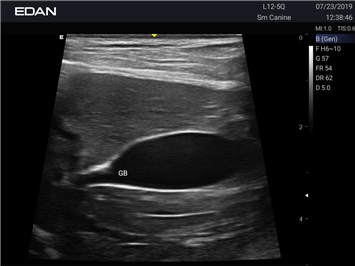

EDAN Acclarix AX2 VET представляет собой специализированную ветеринарную ультразвуковую систему, сочетающую высокую производительность с доступной ценой. Благодаря продуманной конструкции и передовым технологиям, система обеспечивает качественную диагностику животных различных видов.

Революционная платформа визуализации:

• Высокое разрешение для детальной диагностики

• Улучшенная визуализация глубоко расположенных органов

• Технология адаптивной визуализации тканей:

• Непрерывная автоматическая оптимизация изображения

• Адаптация к особенностям анатомии разных видов животных

• Повышенная точность исследований

• Предустановленные протоколы для различных видов животных